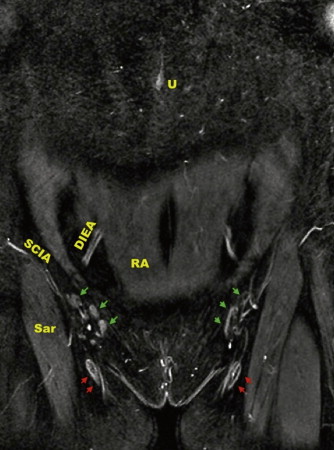

The vascular pedicle for the vascularized groin lymph node flap is commonly based on the superficial circumflex iliac artery (SCIA). This artery originates from the common femoral artery where it makes a short hairpin turn superiorly and laterally as it nearly parallels the course of the inguinal ligament. The flap is drained from both venae commitantes as well as the superficial circumflex iliac vein (SCIV), and to some degree, the superficial inferior epigastric vein (SIEV). The SCIV and SIEV join and continue to inferiorly diverge from the SCIA, and empty into the saphenous bulb near the junction of the greater saphenous vein and the femoral vein.

The lymph nodes supplied by the SCIA are concentrated at the junction of the SCIV and SIEV based on a published anatomic study by the authors. This correlates to a region one-third the distance from the pubic tubercle to the anterior superior iliac spine (ASIS) and 3 cm perpendicularly below this point. These lymph nodes are almost always located above the groin crease but below the inguinal ligament—never below the groin crease. Lymph nodes located below the groin crease typically contribute significantly to drainage of the lower limb, and the sentinel lymph nodes draining the lower limb are commonly along the femoral vessels just below or at the groin crease. Lymph nodes medial to the SIEV may also contribute to lower extremity drainage and may need to be avoided as well. These are solely static anatomic guidelines, not rules, and the physiologic drainage in each individual patient can vary and should be assessed by RLM. In some cases, there are lymph nodes above the groin crease that contribute significantly to lower extremity drainage.

Anatomic landmarks are marked first: a line is drawn from the pubic tubercle and ASIS corresponding to the inguinal ligament. The natural groin crease is marked, the femoral artery is palpated and marked, and the sartorius muscle border is marked. The femoral triangle becomes easily apparent and is the origin of the pedicle. We typically utilize the groin flap as a buried flap without a skin paddle for transfer to the axilla in upper extremity lymphedema. In this case, the incision is planned over the course of the SCIA, which can be localized with a handheld Doppler and/or by using anatomic landmarks: the SCIA courses obliquely approximately 3 cm below the inguinal ligament, but always above the groin crease ( Figure 19.1 ). Incision length depends on the amount of soft tissue desired. If there is a large axillary dead space following extensive scar excision, the incision can be extended laterally to create an appropriately larger flap. The flap width is limited inferiorly by the groin crease but can be extended superiorly as needed. A typical flap dimension is 5 × 10 or 5 × 12 cm. If a distal transfer is planned to the forearm or wrist, the skin paddle is oriented so that the course of the SCIA is centered within it.

The preoperative workup also includes modalities to evaluate outcome, ideally both objective and subjective. We perform preoperative imaging on all patients including MRA to study both donor and recipient anatomy, to evaluate the fluid content in the affected limb, and obtain volumetric measurements. Lymphoscintigraphy and indocyanine green lymphangiography are also performed to obtain a baseline to compare with postoperative imaging. In patients with an axillary dissection, preoperative MRA has revealed a number of significant findings including, axillary vein narrowing or occlusion, and ligation of the thoracodorsal vessels; it has also allowed us to choose the groin donor site with the most lymph nodes and most favorable anatomic layout ( Figure 19.2 ). This is valuable information that can affect the operative plan and reduce uncertainty during the procedure.